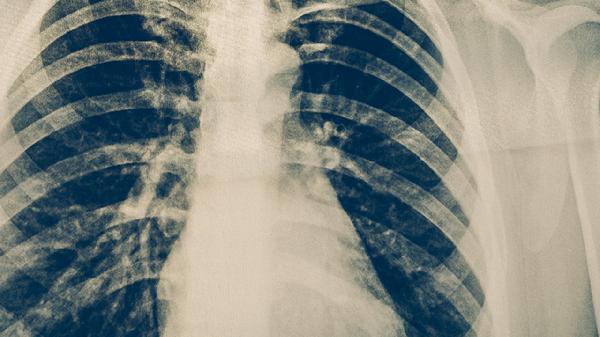

初治肺结核患者采用一线抗结核药物规范治疗时,多数在6个月内痰菌转阴,病灶吸收。完成一年疗程后,痰涂片和培养持续阴性、影像学显示病灶稳定即达到治愈标准。治疗期间需定期复查肝功能、血常规,避免自行停药导致耐药。利福平胶囊、异烟肼片、吡嗪酰胺片等药物联合使用可有效杀灭结核分枝杆菌,但需注意药物性肝损伤等不良反应。

耐药结核病患者即使服药一年也可能未完全治愈,需根据药敏试验调整方案。广泛耐药结核病需使用贝达喹啉片、德拉马尼片等二线药物,疗程显著延长。治疗失败常见于不规则用药、合并糖尿病等基础疾病或免疫抑制状态。痰菌持续阳性者需重新评估治疗方案,必要时行支气管镜活检明确病原学。